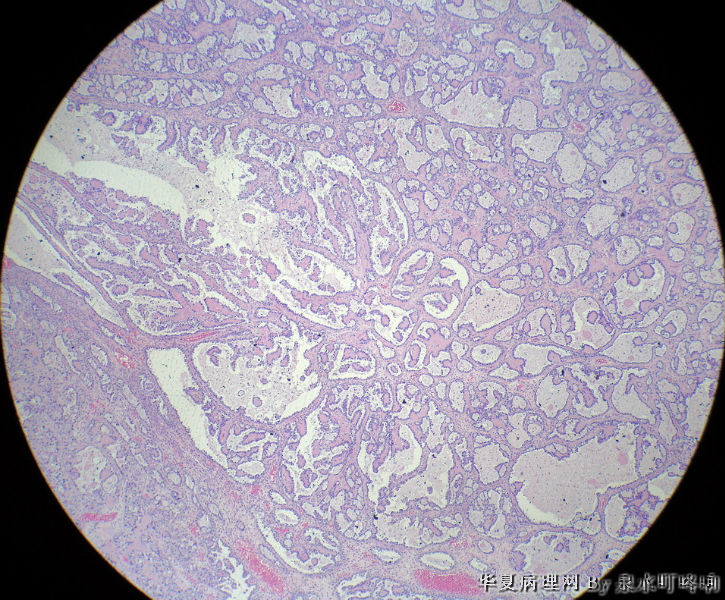

左卵巢肿物

左卵巢肿物图1

名称:图1

描述:1

天津肿瘤医院会诊:混合细胞上皮癌(透明细胞癌+浆液性囊腺瘤+勃勒那氏瘤)。

女,42岁,左卵巢肿物。

大体,灰褐色囊性肿物一个,大小约13×9×8厘米,临床已切开,内容物流失,肿物内壁可见多发乳头,最大4×3×3厘米,小者如绿豆大。